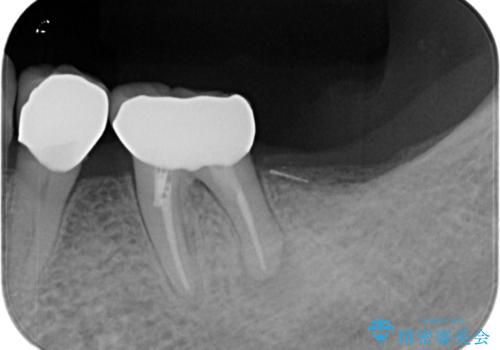

- 左下の大臼歯(6番)の根の治療を行いました。

左下6番の根管治療は六本木院の林院長にお願いしています。